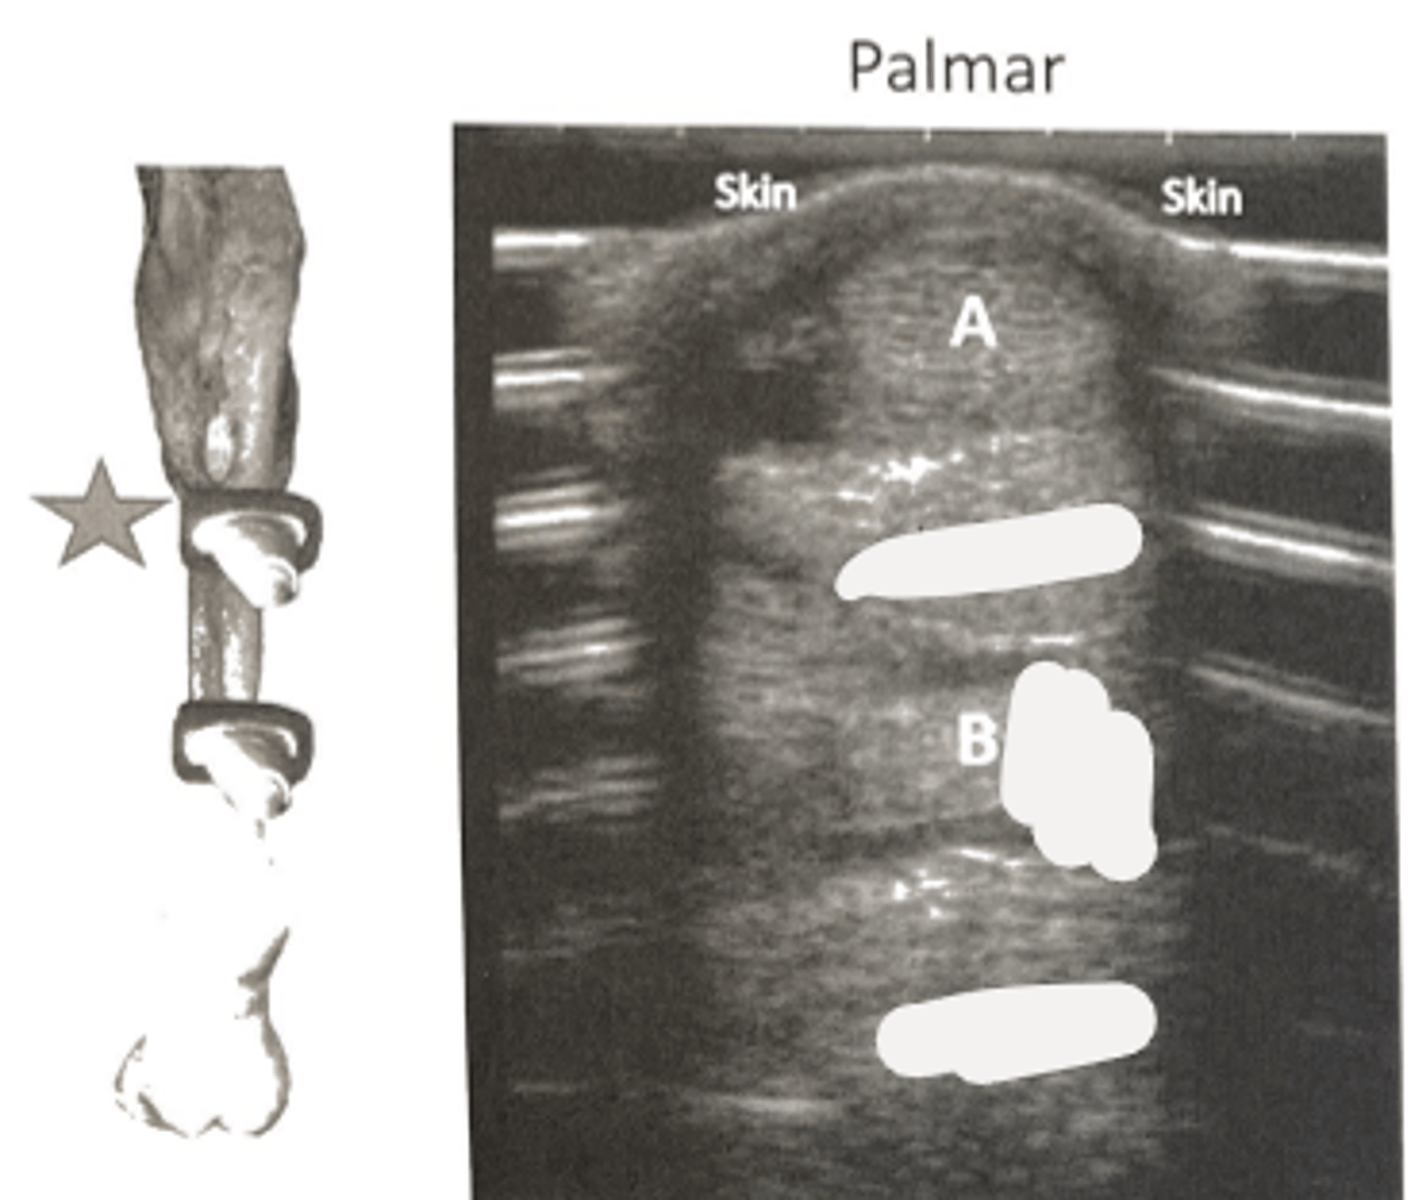

superficial digital flexor tendon

What is A?

accessory ligament of the DDFT (distal check)

What is B?